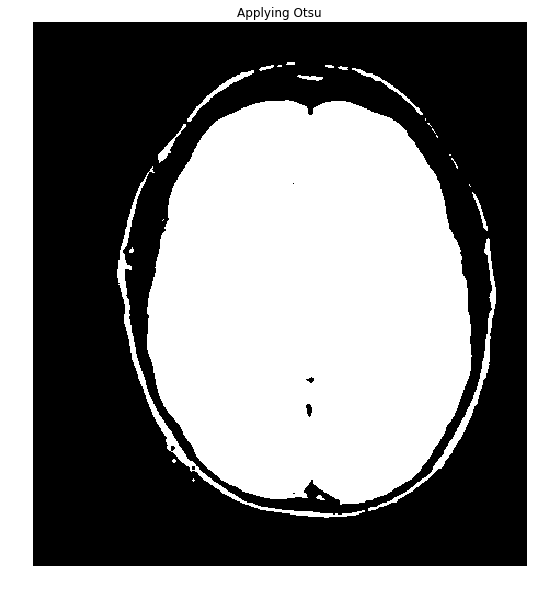

If the pixels in the image can be classified into two different intensity classes, that is, if they have a bimodal histogram, then Otsu's method can be used to threshold them into a binary mask. Let's check that assumption.

Okay, the data is nicely bimodal. Let's apply the threshold and see how we do.

#Threshold the image to binary using Otsu's method

ret, thresh = cv2.threshold(gray,0,255,cv2.THRESH_OTSU)

ShowImage('Applying Otsu',thresh,'gray')